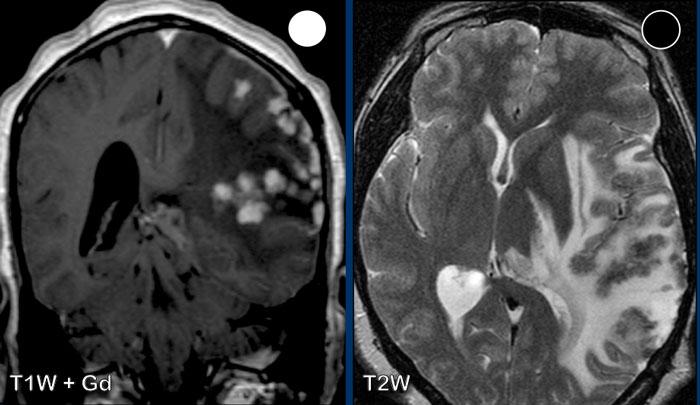

Bệnh nhân này có tiền sử ung thư phổi và nhập viện với các triệu chứng đau đầu và chậm chạp về tâm thần.

Hãy quan sát các hình ảnh trước rồi tiếp tục đọc.

Câu hỏi:

- Các dấu hiệu hình ảnh là gì?

- Chẩn đoán có khả năng nhất là gì?

Hình ảnh

Ghi nhận nhiều tổn thương ngấm thuốc dạng vòng viền liên thông nhau kèm phù não xung quanh ở bán cầu phải.

Vỏ bao tương đối mỏng và đều với hạn chế khuếch tán ở trung tâm.

Có sự lan rộng đến não thất bên phải kèm ngấm thuốc của lớp lót não thất (mũi tên).

Lưu ý thêm hạn chế khuếch tán tại tam giác não thất bên trái.

Nhiều người cho rằng đây là bệnh di căn do tiền sử bệnh, nhưng các dấu hiệu hình ảnh điển hình hơn cho áp xe não kèm viêm não thất, và đây chính là chẩn đoán cuối cùng được xác nhận.